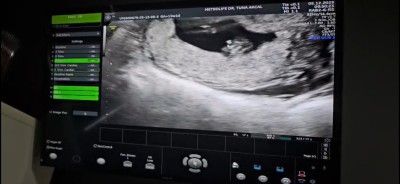

Cinsiyet tahmini olan var mı

Gebelik haftası 13

Bence erkek Rabbim sağlıkla kucagımıza almayı nasip etsin benım 16 haftalık oldu hala göstermıyo kendını:)